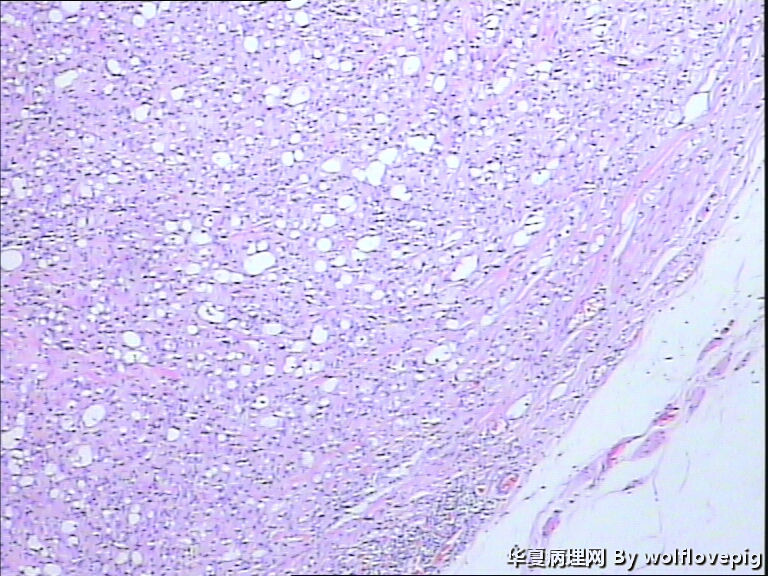

男,60y,左阴囊包块6月,位于附睾尾与睾丸之间,无粘连。灰白结节一个0.7*0.3*0.3,切面灰白、实体 、质韧。

典型的腺瘤样瘤